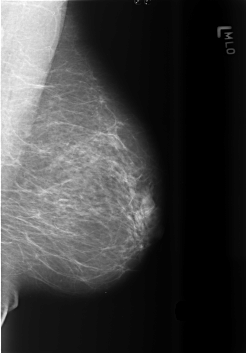

B_3432_1.LEFT_MLO

LEFT_MLO LINES 5648 PIXELS_PER_LINE 3928 BITS_PER_PIXEL 12 RESOLUTION 50 NON_OVERLAY